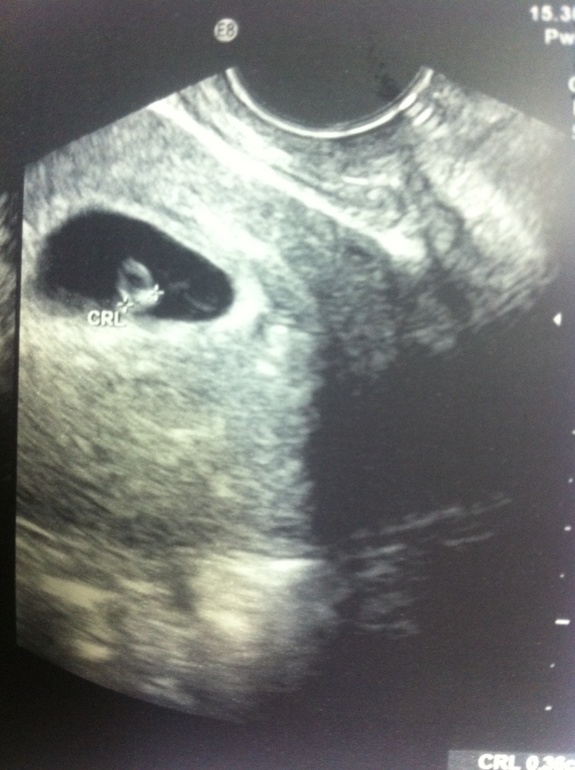

Моя буська :*** :)

себе не страшно колоть...вот кому-либо другому страшновато ваще не верится, что они такие малюськи) всего 4 мм а уже сердце стучит

агась,я как домой зашла сразу к линейке :))) тааакая маська !!! Моя любимая маська !

Ура!!!!! Поздравляю)))) красота какая:))) 5,5 срок от зачатия,да? а вверху над эмбрионом белый полукруг полу прозрачный это что?!)

да,от зачатия :) не знаю,сам эмбрион наверно :)))